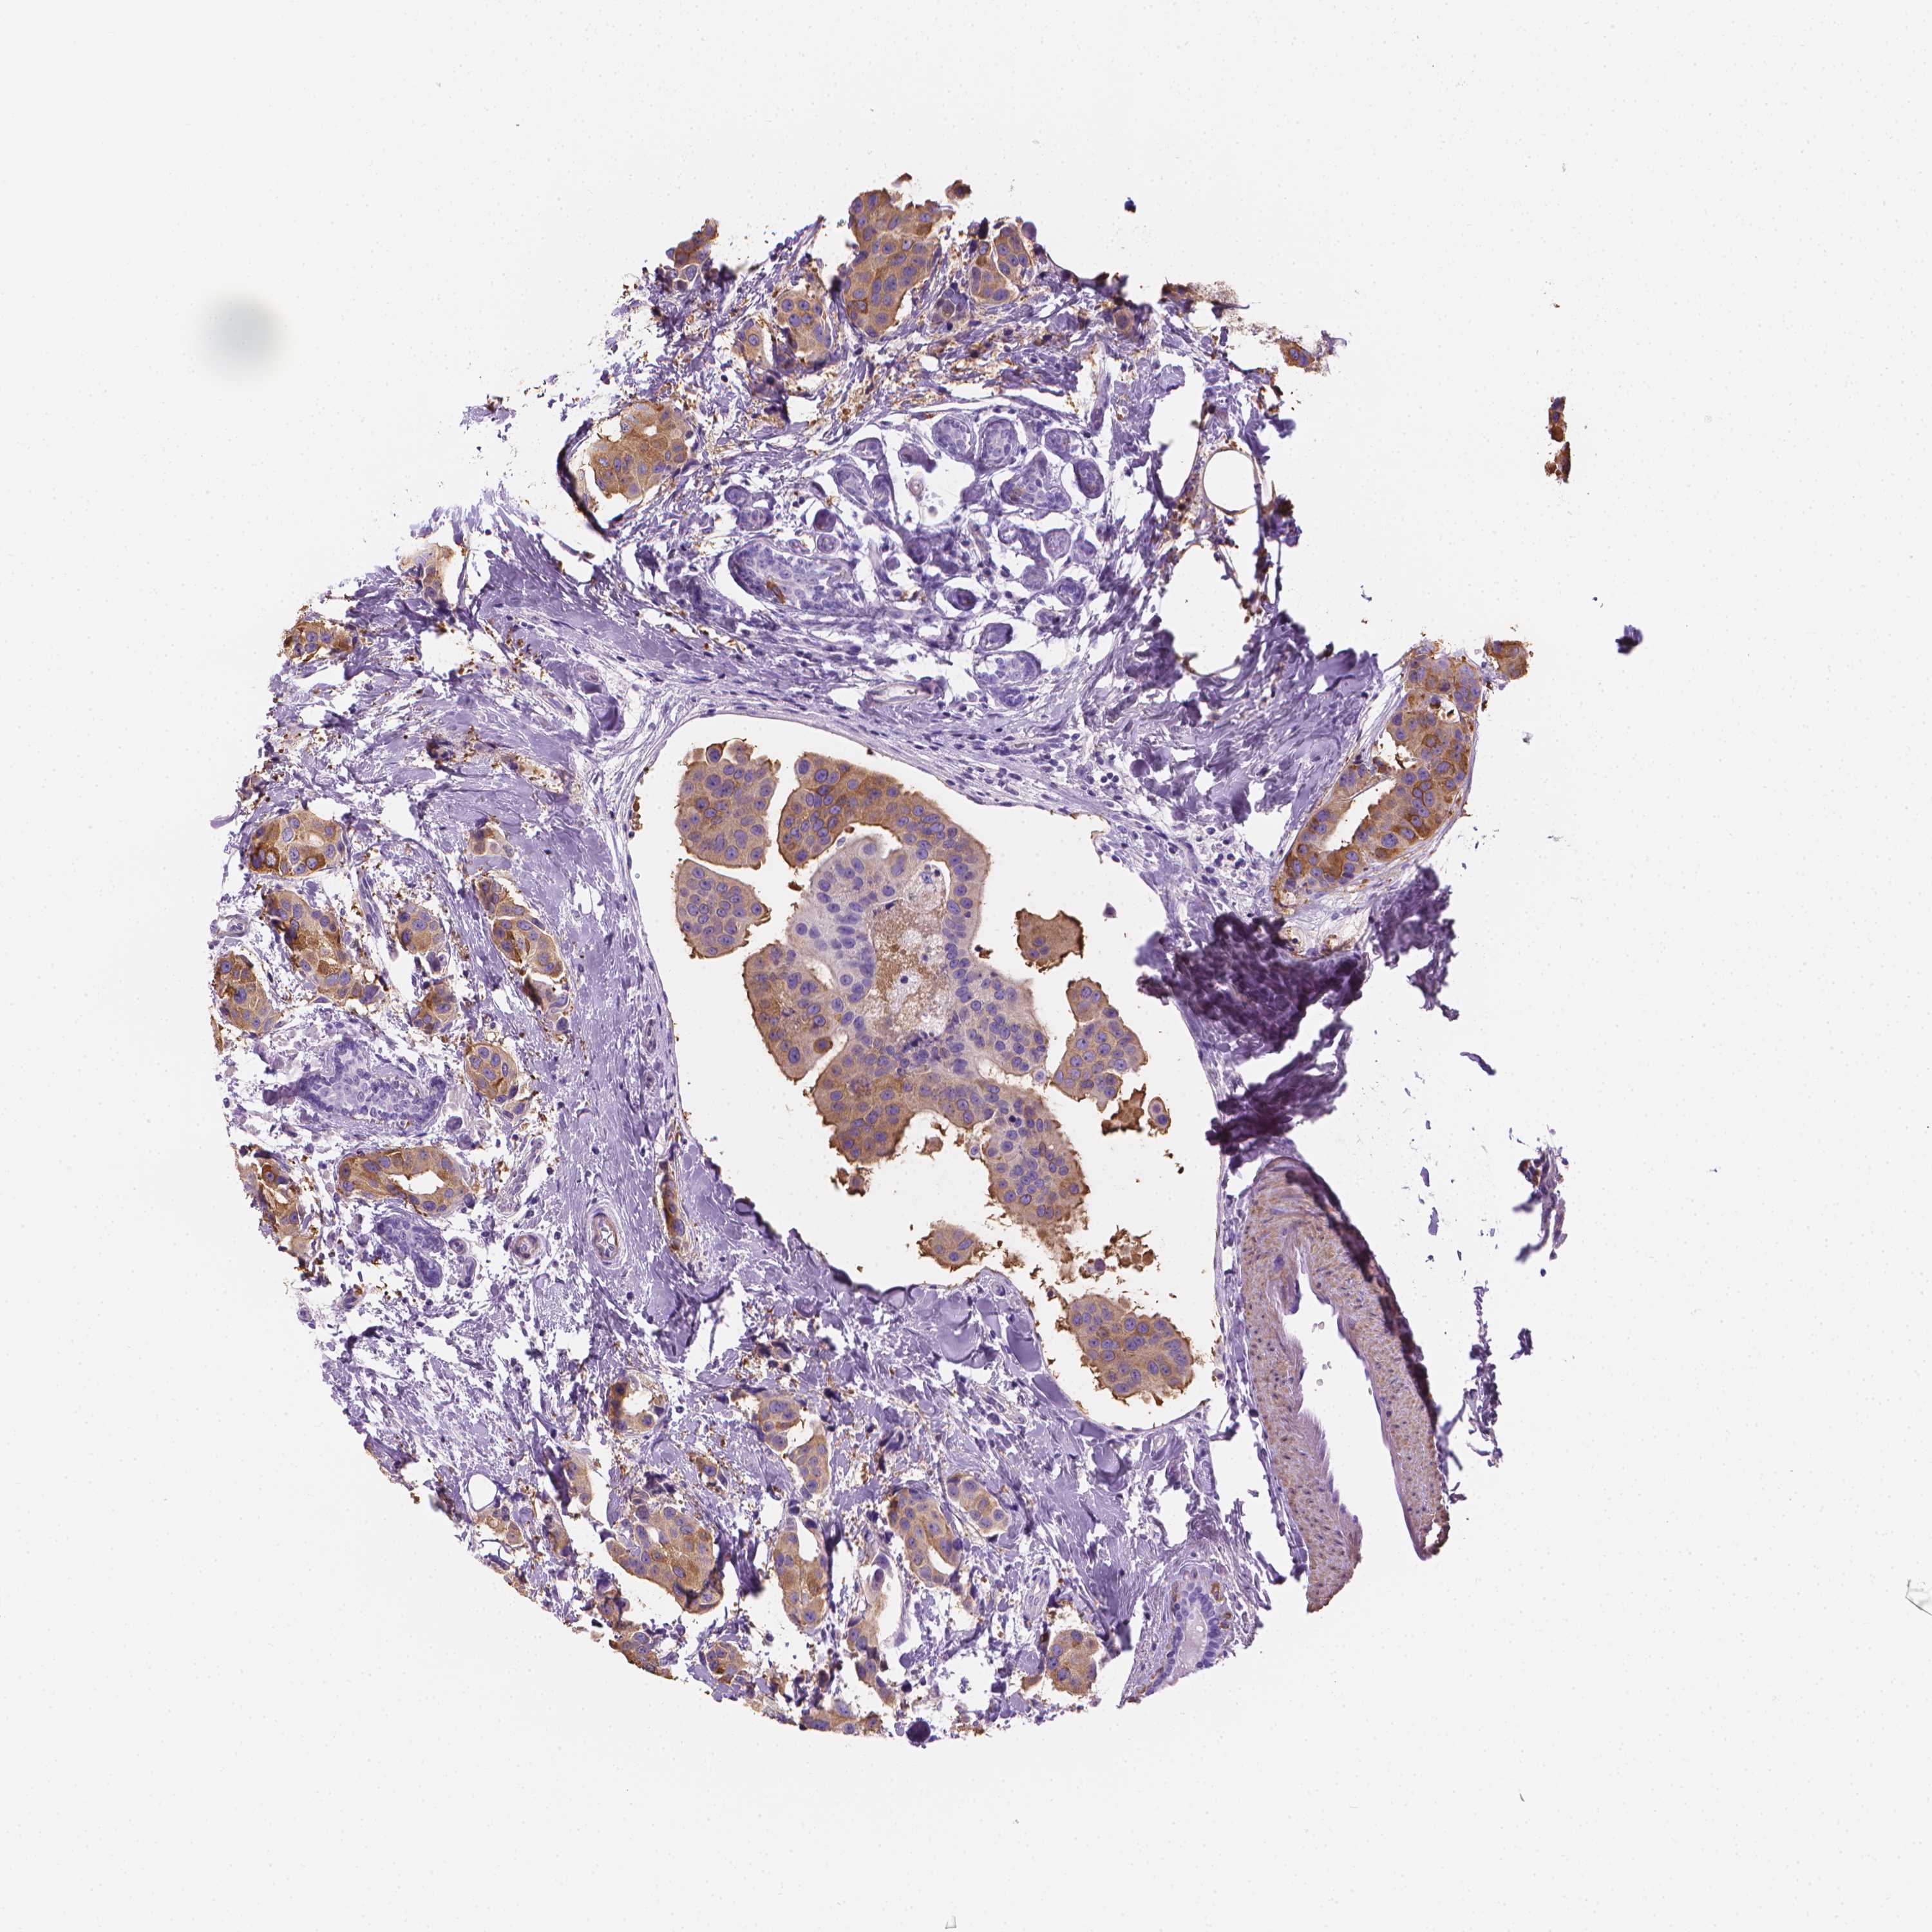

CANCER BREAST CANCER Show tissue menu

BRCA TCGA BRCA VALIDATION PROTEIN EXPRESSION

ANTIBODIES

AND

VALIDATION